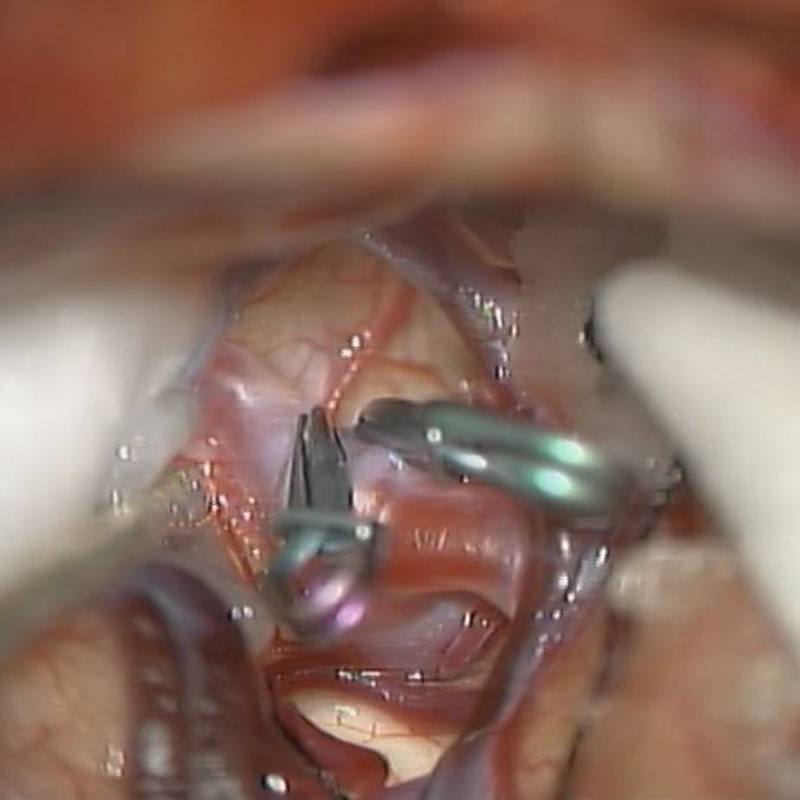

クリップ前

クリップ後

術後血管撮影